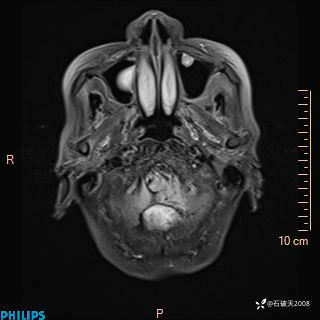

女 86岁 主 诉:乏力1月

现病史:患者1月前活动出现双下肢乏力,无头晕、头痛、恶心、呕吐、肢体活动不利,休息后缓解,间断断发作,症状进行性加重,在家口服药物治疗(具体不详),效差,为进一步诊治,来我院,门诊按“乏力”收住我科,患者自发病以来,神志清,精神稍差,饮食睡眠欠佳,大小便正常,体重未见明显改变。

增强冠状位

增强矢状位